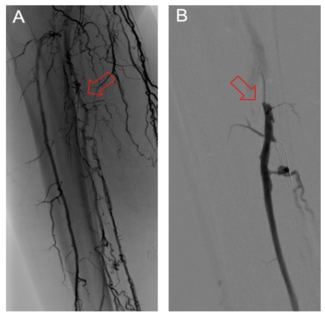

The primary objective of this study was to describe a novel classification system to characterize patterns of failure in deep venous arterialization (DVA) and suggest intervention strategies that correlate with these patterns.